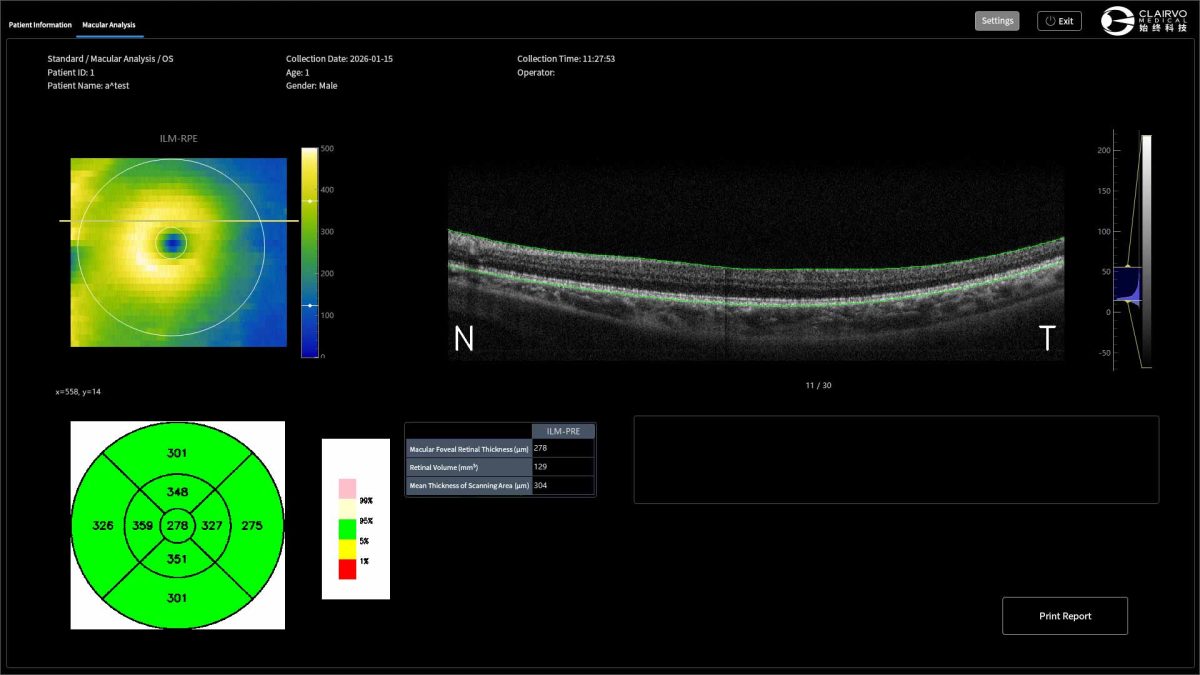

Intelligent Analysis System

An Al-powered imaging analysis and platform enables eficient screening of fundus lesions and supports  clinical decision-making,improving diaanostic accuracy and workflow efficiency.